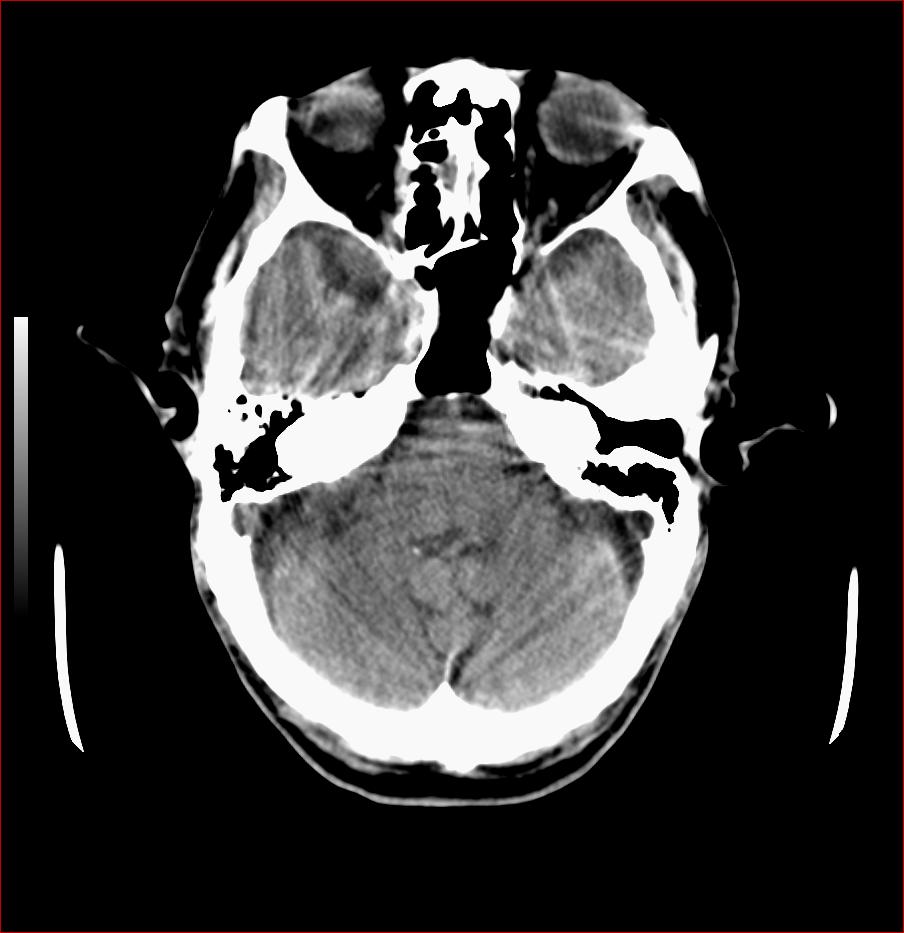

男,84岁,左下肢无力伴口角歪斜1天,血压160/80。请问一下双侧基底节区是脑梗塞吗?

基底节区脑梗塞,脑萎缩,左侧小脑脑梗塞

双侧基底节多发腔梗,皮层下动脉硬化性脑病

1.两侧基底节区及右顶深部脑梗塞。2.右侧外囊区脑软化灶。3.脑萎缩。4.脑白质脱髓鞘改变。

1.双基底节区及双顶深部脑梗塞;2.右外囊区软化灶;3.皮层下动脉硬化性脑病.